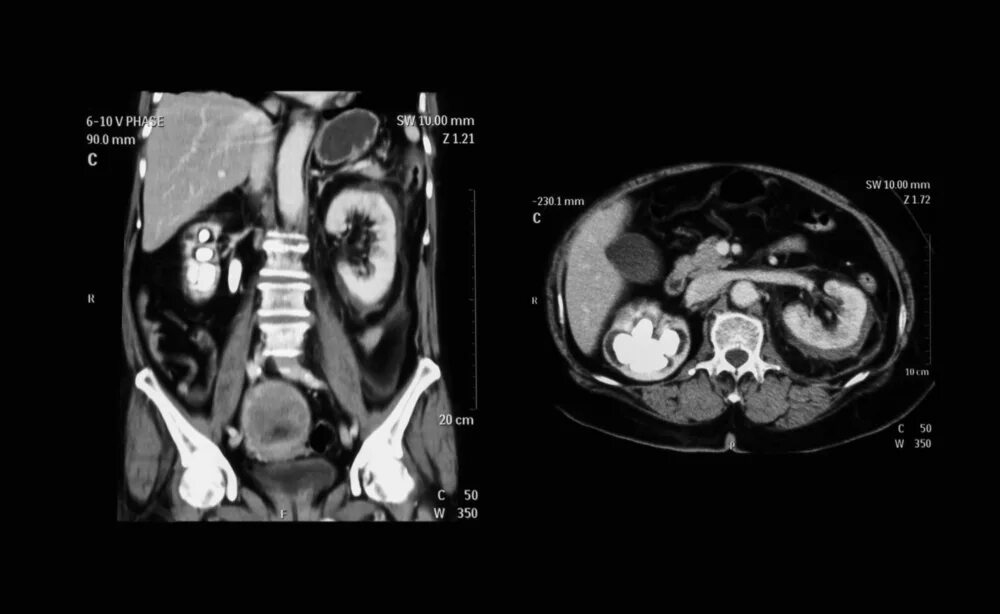

Как подготовиться к мскт брюшной